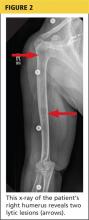

The patient continued to experience vague abdominal, back, and rib pain that seemed to migrate daily and worsened with movement. A skeletal x-ray was performed and revealed numerous lytic lesions of the skull (Figure 1), midright humerus (Figure 2), and distal left radius.